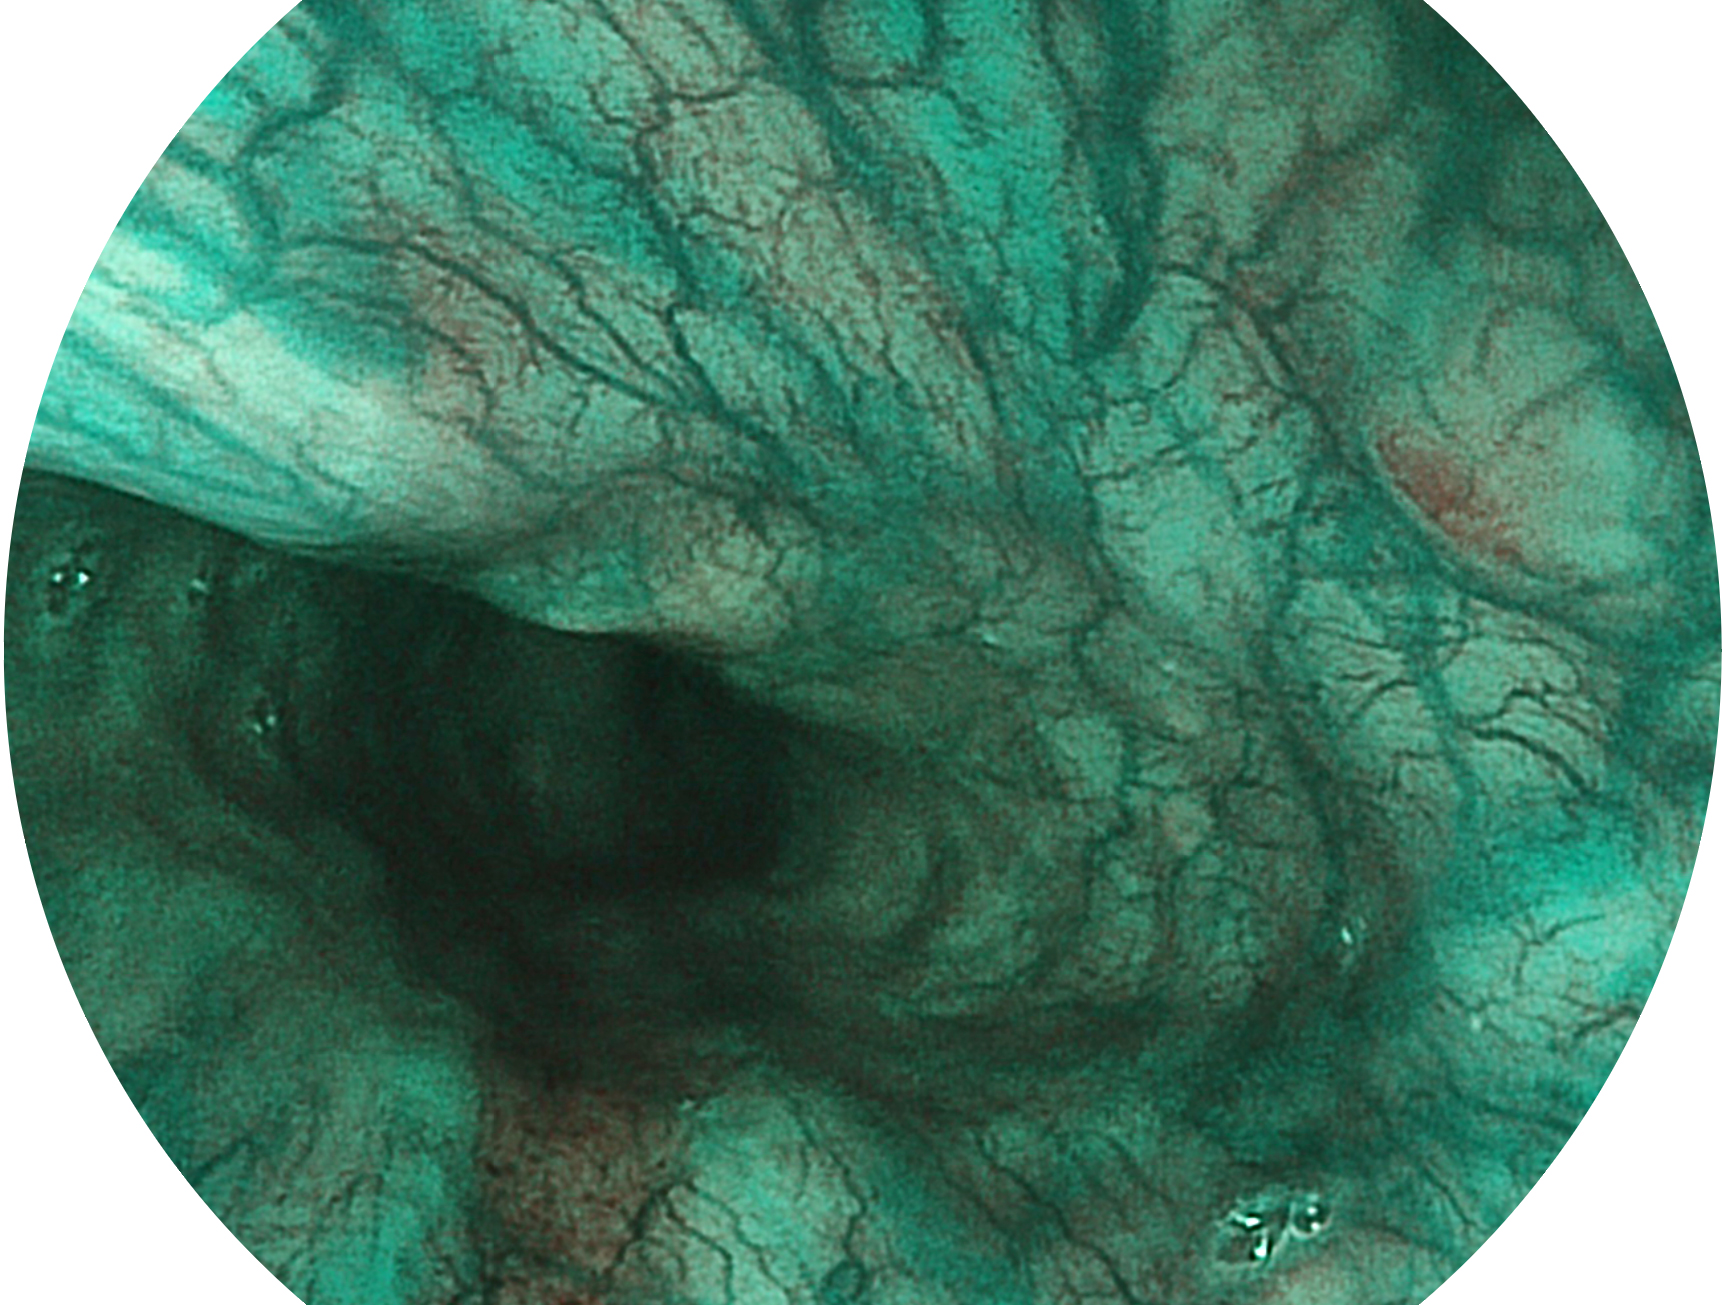

开立新开发的内镜染色技术,主要是基于多波长LED 光源的开发,VLS-55Q 四波长LED 光源是由四个不同颜色的LED光按照相应照明模式所规定的特定发光比例进行合束后形成,合束后形成的照明光的光谱由红光、绿光、蓝光及蓝紫光这四个不同的波段范围构成。具有更高光谱自由度,通过光谱比例的控制,实现了聚谱成像技术,英文全称为“Spectral Focused Imaging, SFI”,缩写为“SFI”和光电复合染色成像技术,英文全称为“Versatile Intelligent Staining Technology, VIST”,缩写为“VIST”。